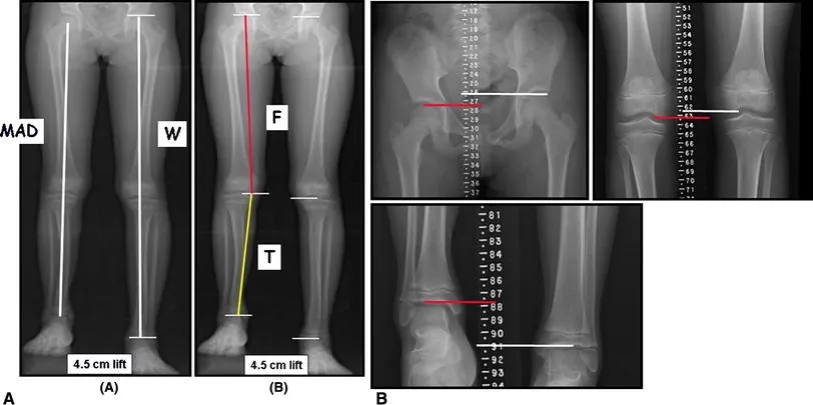

- W niektórych przypadkach do potwierdzenia nierówności anatomicznej konieczne jest badanie RTG.

Kiedy mówimy o skróceniu anatomicznym, mamy na myśli sytuację, w której jedna z kości udowa lub piszczelowa jest faktycznie krótsza od drugiej. Przyczyny mogą być różne: wady wrodzone, przebyte urazy (np. złamania z uszkodzeniem nasady kości), choroby zapalne kości czy stany po zabiegach operacyjnych. W takich przypadkach, aby jednoznacznie potwierdzić różnicę w długości kości, często konieczne jest wykonanie badania radiologicznego (RTG). To właśnie ten typ nierówności jest najbardziej bezpośrednią przyczyną asymetrii.

W gabinecie fizjoterapeutycznym standardem jest precyzyjny pomiar długości kończyn dolnych taśmą centymetrową. Wykonujemy go zazwyczaj w pozycji leżącej na plecach. Aby ocenić długość bezwzględną (czyli rzeczywistą długość kości), mierzymy odległość od przedniego górnego kolca biodrowego (ASIS) do kostki przyśrodkowej. Następnie, aby ocenić długość względną, która uwzględnia ustawienie miednicy, mierzymy odległość od pępka do kostki przyśrodkowej. Powtarzamy pomiar dla obu nóg. Kluczowe jest tutaj precyzyjne zlokalizowanie punktów pomiarowych oraz zapewnienie, aby miednica pacjenta była ustawiona symetrycznie w trakcie badania. To daje nam konkretne liczby, które są podstawą do dalszej analizy.

Test podkładkowy (Block Test): Jak specjalista precyzyjnie ocenia poziom Twojej miednicy?

Kolejną bardzo ważną i często stosowaną metodą jest test podkładkowy, znany również jako Block Test. Pacjent staje prosto, a fizjoterapeuta umieszcza pod piętą nogi, która według wstępnych obserwacji jest krótsza, drewniane podkładki o różnej grubości. Obserwujemy przy tym tylne górne kolce biodrowe (PSIS) są to punkty kostne z tyłu miednicy. Celem jest dobranie takiej grubości podkładek, aby PSIS znalazły się na tym samym poziomie. Gdy miednica jest wyrównana, możemy dokładnie określić, o ile centymetrów jedna noga jest krótsza od drugiej. To badanie pozwala nam ocenić, jak duża jest nierówność i jak wpływa ona na ustawienie miednicy.